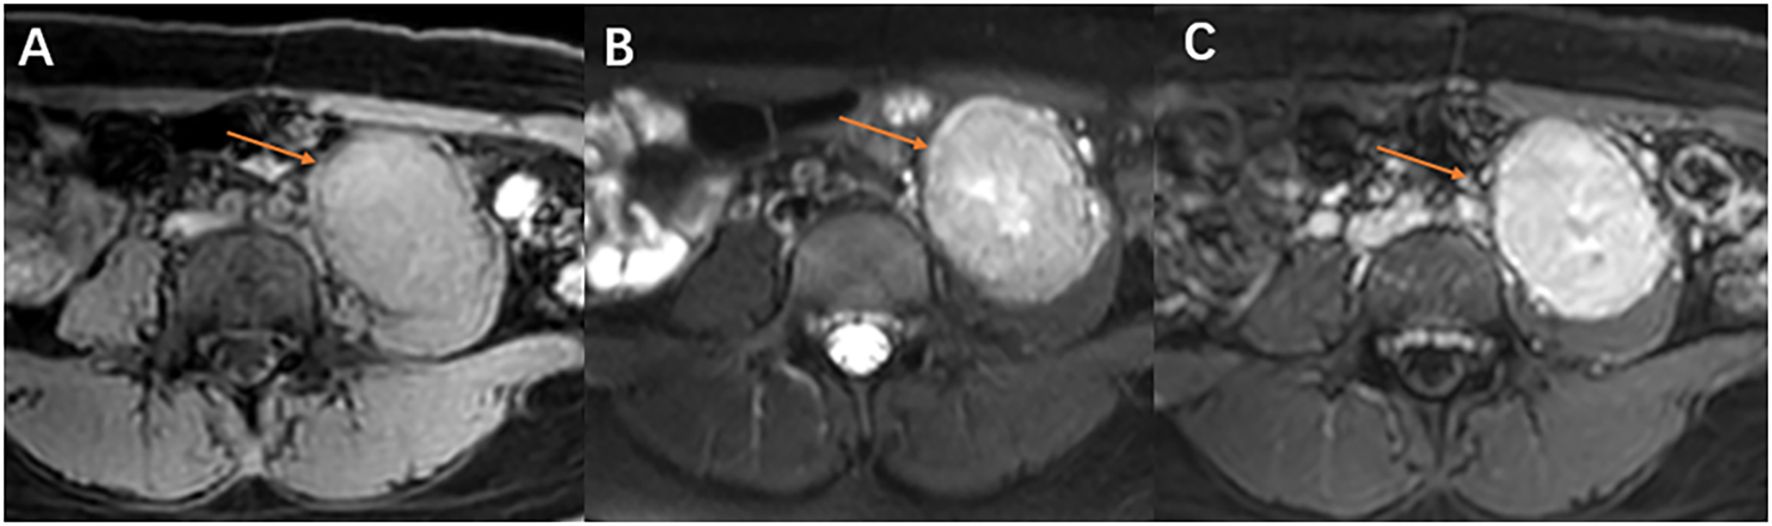

Alveolar soft part sarcoma (ASPS) is an infrequent and malignant soft tissue tumor with an elusive tissue origin. Its occurrence in the retroperitoneal psoas major muscle is extremely rare. The tumor's deep retroperitoneal location, complex anatomy, and hypervascularity pose challenges to preoperative diagnosis and surgical intervention. This case report presents a 21-year-old female diagnosed with left retroperitoneal psoas major ASPS. Advanced imaging modalities, such as computed tomography (CT) multidirectional reconstruction, magnetic resonance imaging (MRI), and three-dimensional (3D) rendering, were utilized. These imaging techniques not only clearly depicted the tumor's characteristics but also its spatial relationships with surrounding tissues and the vascular network. The detailed preoperative vascular assessment enabled the surgical team to comprehend the tumor anatomy and meticulously plan the approach, thus significantly reducing surgical risks and potential complications. The procedures and outcomes of this case offer valuable insights for clinical practice, highlighting the crucial role of imaging in the diagnosis and treatment of rare ASPS cases.